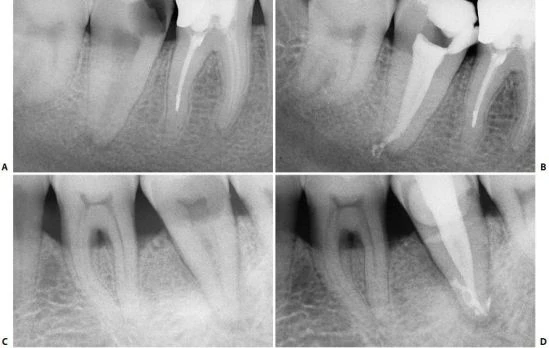

Khi có sự hiện diện của ống gần cong – và vì vậy chân răng chứa ống tủy congnày – sử dụng phương pháp dùng file “chống đoạn cong” là điều bắt buộc khi chuẩn bị ống tủy những chân này. Ống gần của răng cối lớn một dưới cùng với ống gần ngoài của răng cối lớn một trên là 2 vị trí thường xảy ra mài mòn, xuyên thủng nhất (hình 11.118).

Hình 11.118. Bỏ qua việc áp dụng phương pháp “chống đoạn cong” dẫn đến kết quả mài mỏng quá mức thành chân răng và gây xuyên thủng A. Phim trước điều trị. Chú ý độ mỏng của chân gần và độ cong nhẹ của nó. B. Phim sau điều trị: thành xa của chân gần bị mài thủng.

Trong 10% trường hợp, 2 ống tủy có giao nhau tại chóp với 1 lỗ chóp (hình 11.119). Sự giao nhau này, theo quan điểm của tác giả, dễ dàng nhận thấy sau khi làm sạch và tạo hình ít nhất một ống tủy hơn là so với tại thời điểm bắt đầu điều trị. Quả thật, 2 cây file nhỏ có thể đồng thời đi vào 2 ống tủy khác nhau xuống chóp, thậm chí nếu 2 ống tủy giao nhau tại cùng 1 lỗ chóp, nếu nó đủ rộng thì có thể để 2 file đi qua. Đưa 1 dụng cụ lớn hơn vào 1 ống tủy và 1 cái nhỏ hơn vào ống tủy kia có thể dẫn đến cây nhỏ bị gãy.

Hình 11.119. Phim sau điều trị cho thấy các ống gần gặp nhau tại cùng một lỗ chóp.

Theo quan điểm của tác giả, sử dụng côngutta-percha trong 1 ống tủy vừa được chuẩn bị và 1 dụng cụ nhỏ ở ống chưa chuẩn bị thì an toàn hơn. Nếu 2 ống tủy giao nhau, sẽ có dấu in lại của dụng cụ trên côn gutta-percha (hình 11.120). Vì việc mài hết thành ống tủy thường gặp ở ống gần ngoài hơn là ống gần trong của răng cối lớn một dưới. Khuyên nên luôn luôn bắt đầu làm sạch và tạo hình 2 ống của chân gần, đầu tiên là ống gần trong sau đó dùng 1 cây côn gutta-percha và 1 dụng cụ nhỏ tìm xem có giao nhau giữa ống gần ngoài và ống gần trong tại cùng một lỗ chóp không.

Cần tiết kiệm phần ngà của ống gần ngoài bằng cách mở rộng ống tủy ít, làm giảm nguy cơ mài hết thành chân răng gây thủng.

Hình 11.120. A, B. Đặt gutta-percha vào trong ống tủy gần trong đã được làm sạch và tạo hình, còn file 8 được đặt vào trong ống gần ngoài chưa được sửa soạn. Tại chỗ giao nhau, trâm đâm xuyên qua côn gutta percha.